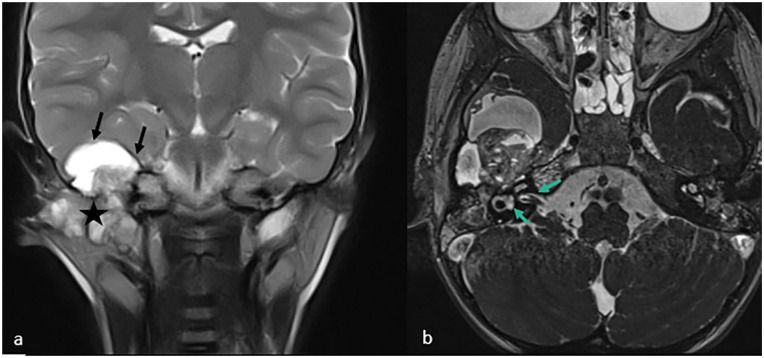

Infantile myofibromatosis is a proliferative disorder occurring during infancy and early childhood, marked by the development of nodular or diffuse lesions consisting of various mesenchymal elements. Intracranial involvement is infrequently reported. Here, we present the case of a 3-year-old girl exhibiting a rare manifestation of IM with intracranial parenchymal involvement, displaying a histological pattern documented in existing literature on patients with infantile myofibromatosis. Subsequent MRI follow-up revealed no signs of recurrence.